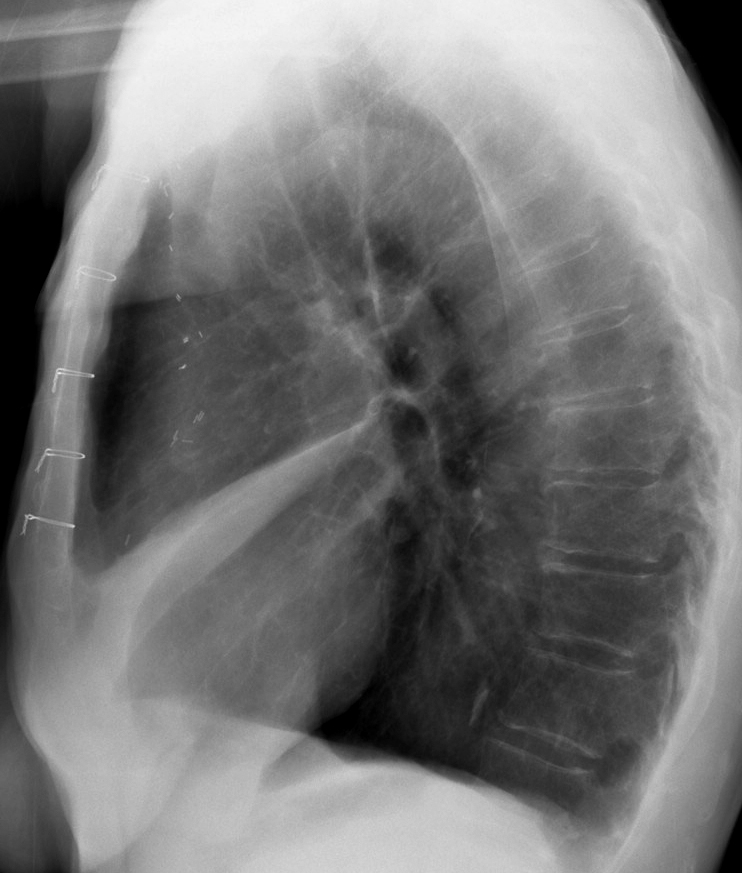

Gallery Lobar Collapse RML Collapse Case 3 Lat

Case 3 Lat